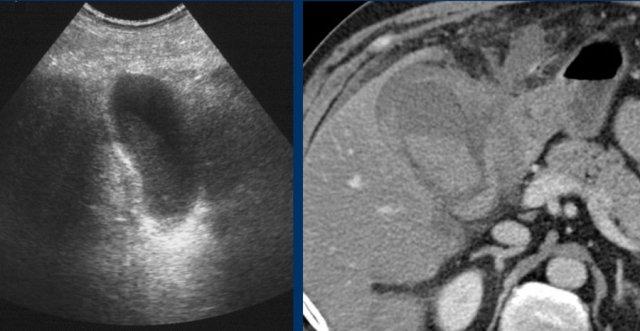

Bệnh nhân béo phì với đau thượng vị cấp tính.

Siêu âm cho thấy sỏi túi mật và dày thành, gợi ý viêm túi mật cấp.

CT thực hiện tiếp theo đã phát hiện bản chất thực sự của các triệu chứng: viêm tụy cấp do sỏi mật với dày thành túi mật thứ phát.